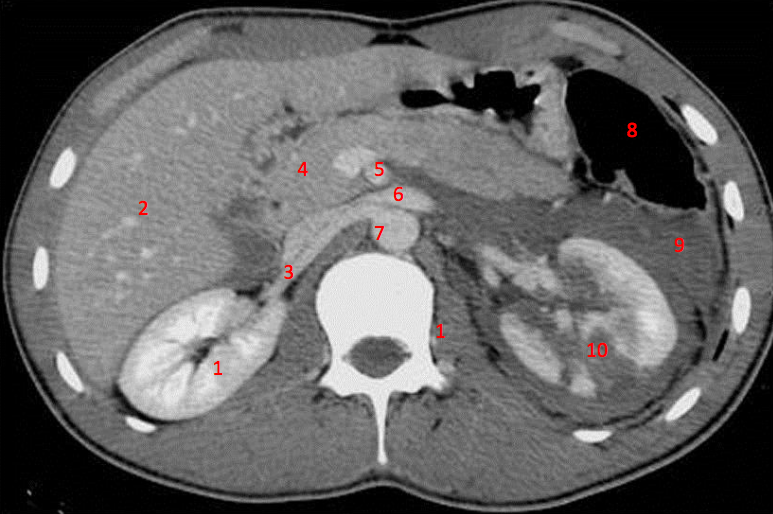

14

Number 4?

Rt diaghragmatic crus

15

Number 7?

Bowel (probably large)

21

Number 5?

Rt ureter

22

Number 6?

Descending colon

23

Number 9?

Superior mesenteric artery

24

Number 8?

Abdominal aorta

26

Rt erector spinae muscle

28

Rt renal artery

Lt common iliac artery

30

Body of pancreas

31

Number 3?

Portal vein

36

Splenic vein

42

Rt psoas

45

Rt psoas muscle

Lt renal vein

Number 10?

Rt kidney

Duodendum

Aorta

Number 2?

Ascending colon

Traumatic laceration of Lt kidney

Lt erectae spinae muscle